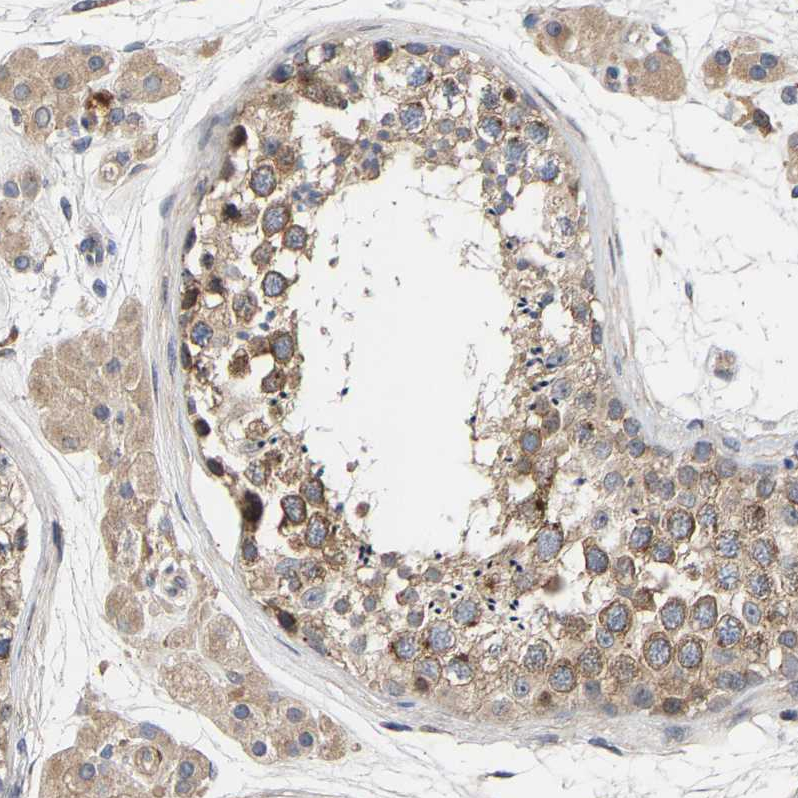

Immunohistochemical staining of human cerebral cortex, gastrointestinal, lymphoid tissues and testis using Anti-CCDC155 antibody HPA019937 (A) shows similar protein distribution across tissues to independent antibody HPA019940 (B).